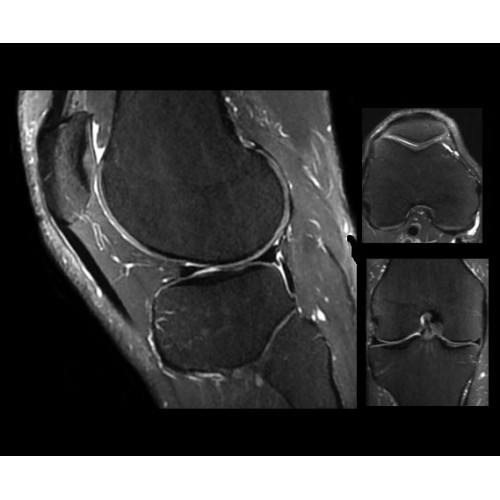

SIGNA PET/MR 3.0T — это гибридная система, в которой совмещаются две принципиально разные технологии — магнитно-резонансную томографию (МРТ) и позитронно-эмиссионную томографию (ПЭТ). Система отличающийся высокой чувствительностью и эффективностью и предназначена для диагностики в области онкологии, неврологии, кардио-васкулярных исследований, исследований воспалительных процессов.

Компания GE Healthcare представляет революционную, полностью интегрированную систему SIGNA PET/MR1, в которой сочетаются времяпролетная технология (TOF) и возможности напряженности магнитного поля 3.0 Тл. Мы поможем вам поднять исследования на более высокий уровень. SIGNA PET/MR позволяет достичь впечатляющей точности и скорости исследований, а благодаря новейшей технологии реконструкции Q.Clear2 качество изображений улучшается в два раза. Кроме того, в систему включен полный набор клинических приложений и гибких катушек для проведения любых видов исследования, открывая для вас возможности визуализации, о которых вы даже не догадывались.

Впечатляющие клинические возможности

Система SIGNA PET/MR предлагает впечатляющие клинические возможности и открывает доступ к наиболее полным пакетам программных приложений.